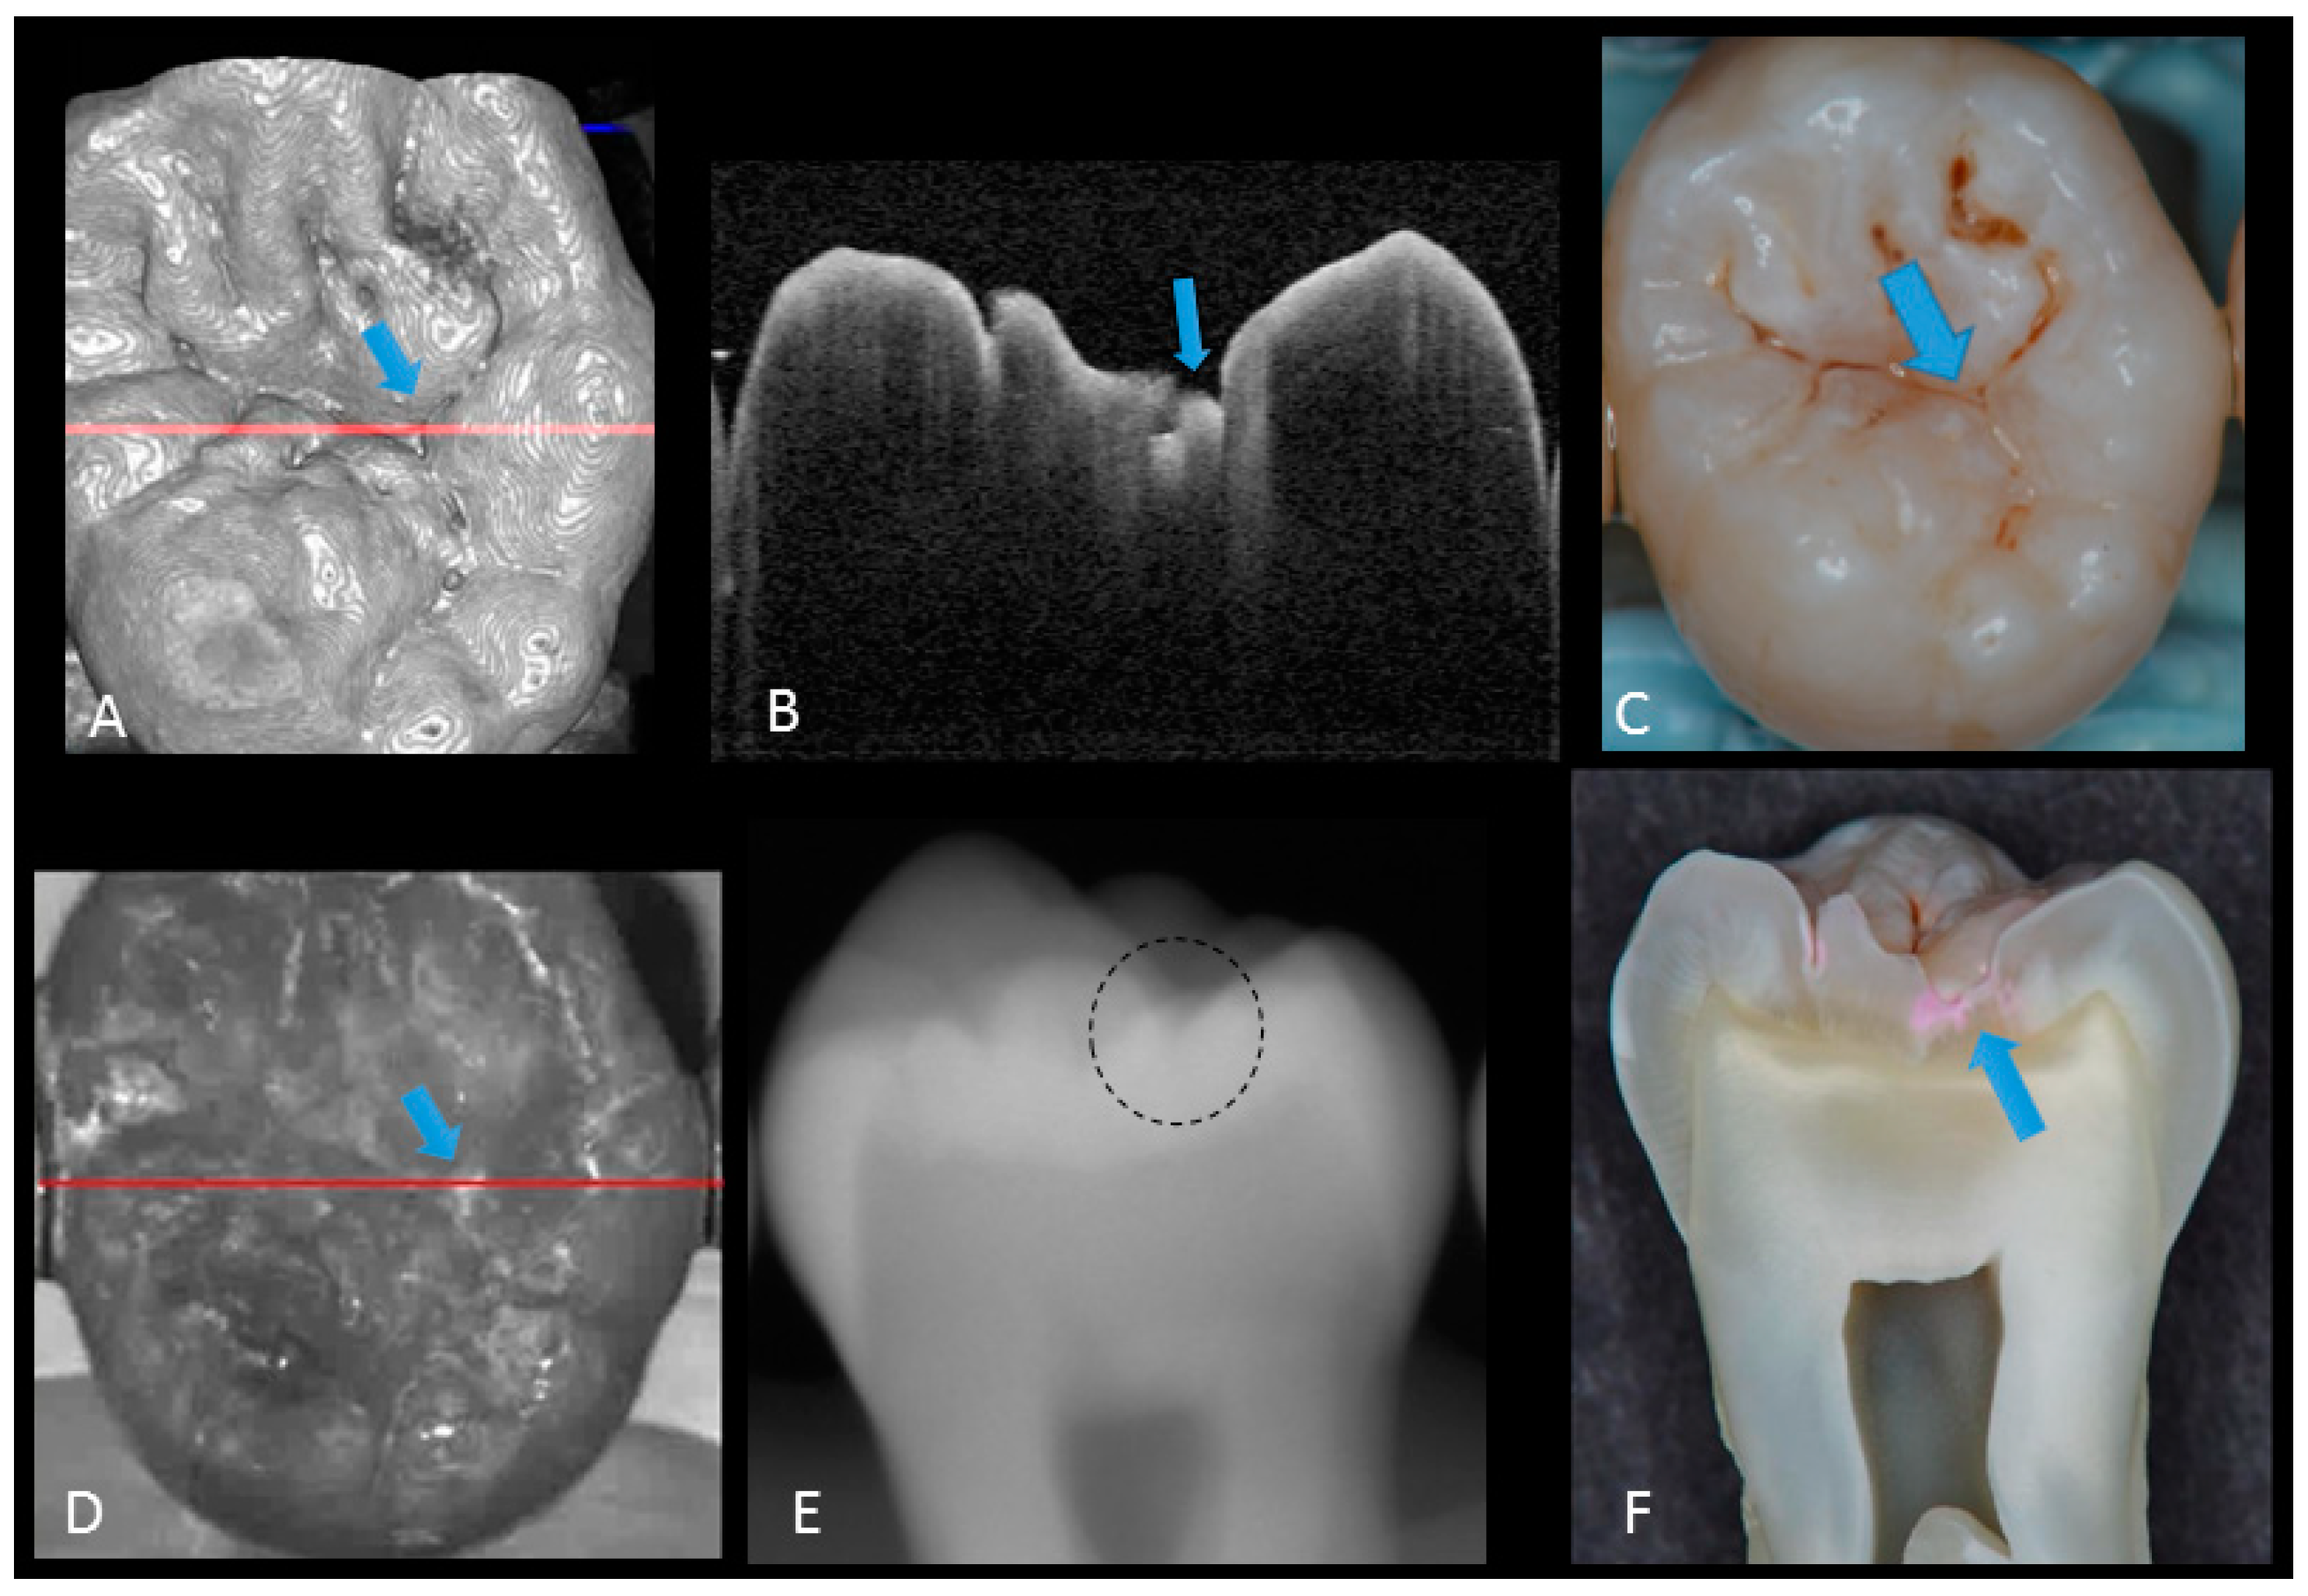

2. Materials and Methods

2.1. Specimen Preparation

2.2. Photography and X-ray Imaging

2.3. Optical Coherence Tomography

2.5. Validation of the Actual Scores